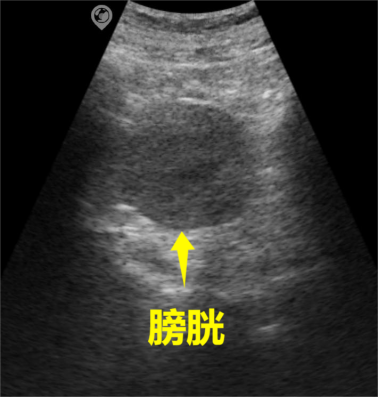

SonoMaxx Handheld Ultrasound MX6 for Bladder Scanning

4. Anechoic: Normal human blood, urine, etc., appear as anechoic, and pathological changes such as effusions, cysts, abscesses, etc., also appear as anechoic.